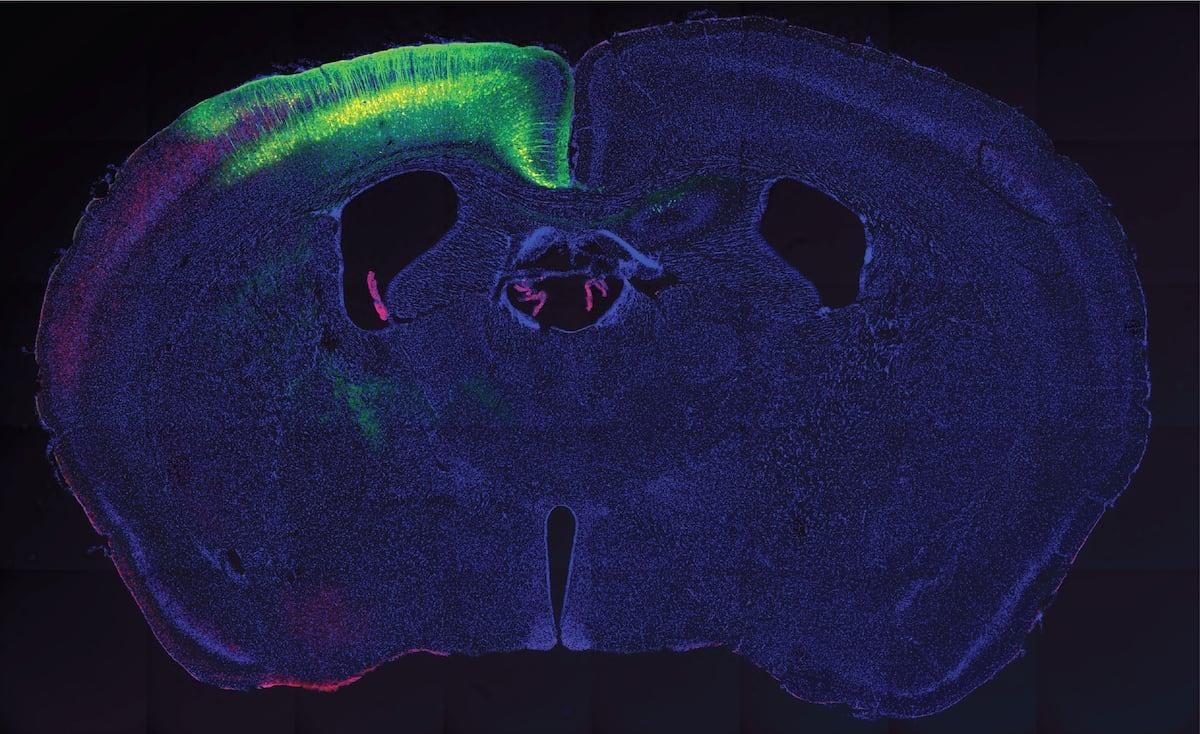

Pesquisadores mostraram que é possível ativar neurônios de mamíferos com ultrassom ao introduzir neles uma proteína sensível a esse tipo de estímulo. Em experimentos com ratos, genes foram modificados para que certas células neurais expressassem uma variante humana de TRPA1, um canal iônico mecanossensível pertencente à família TRP, conhecida por responder a temperatura e estímulos mecânicos.

Depois de expressar TRPA1 em grupos específicos de neurônios, os cientistas colocaram um transdutor de ultrassom sobre a cabeça dos animais. Ao disparar ondas sonoras em frequências e intensidades definidas, observaram que apenas as células com a proteína se ativavam, gerando, por exemplo, movimentos precisos nas patas dos ratos. Sem TRPA1, o ultrassom não tinha esse efeito seletivo.